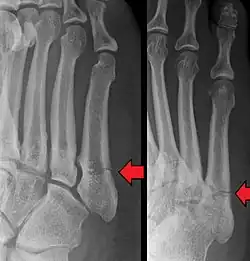

Pseudo-Jones fracture

Other proximal fifth metatarsal fractures exist, although they are not as problematic as a Jones fracture. If the fracture enters the intermetatarsal joint, it is a Jones fracture. If, however, it enters the tarsometatarsal joint, then it is likely an avulsion fracture caused by pull from the fibularis brevis tendon. An avulsion fracture at the base of the fifth metatarsal is sometimes called a "dancer's fracture" or a "pseudo Jones fracture", and usually responds readily to non-operative treatment.[18] The X-ray appearance of the developmental "apophysis" in this area may have some resemblance of a fracture, but is not a fracture; it is the secondary ossification center of the metatarsal bone. It is a normal finding that occurs at this site in adolescents.[19] If an injury to that area has occurred, the physician is often able to interpret certain radiographic clues to make the differentiation. An avulsion fracture at this location is typically extra-articular and oriented transversally as compared to the longitudinal orientation of an unfused apophysis.[19]